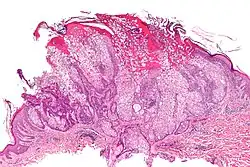

| Micrograph of a sebaceous adenoma, as may be seen in Muir–Torre syndrome. H&E stain. | |